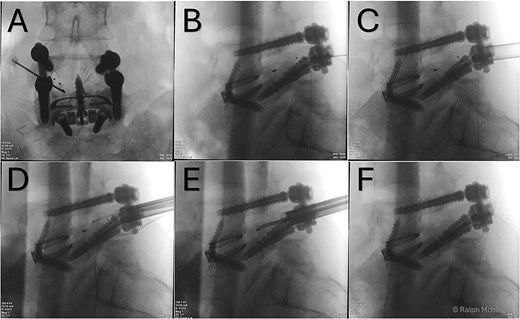

Stage two: endoscopic TLIF cage removal and Rhizolysis

After an adequate interval recovery of 3 days, the patient underwent the second stage of minimally invasive removal of the TLIF cage via an endoscopic approach. The Elliquence Stenosis endoscopic system was used (Elliquence, USA) for TLIF retrieval. Under fluoroscopic guidance, the TLIF cage was identified with a dilator positioned directly superficial to the cage, then a 10 mm working channel positioned to insert the endoscope (Fig. 3). Dissection of the TLIF cage (Fig. 4), mobilization, and retrieval (Fig. 5) was achieved with relative ease (Video 1). Using constant irrigation through the endoscope, this assisted with both hemostasis and hydrodissection of the tissue planes around the cage to aid removal. Hemostasis was achieved, and the wound was closed in standard fashion.

(A) AP X-ray. Initial needle localization over the TLIF cage. (B) Lateral X-ray with needle positioned on posterior aspect of TLIF cage. (C) Working channel positioned immediately posterior to cage. (D) RF diathermy to dissect around cage (see Video 1). (E) Dissection around cage using multiple instruments. (F) Post removal of cage, with no TLIF device evident.